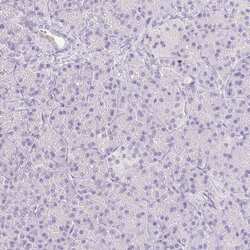

Supportive validation

- Submitted by

- Invitrogen Antibodies (provider)

- Main image

- Experimental details

- Immunohistochemical analysis of EMX2 in human epididymis and pancreas tissues using a EMX2 polyclonal antibody (Product # PA5-84687). Corresponding RNA-seq data are presented for the same tissues.

- Submitted by

- Invitrogen Antibodies (provider)

- Main image

- Experimental details

- Immunohistochemical analysis of EMX2 in human pancreas using a EMX2 polyclonal antibody (Product # PA5-84687). The analysis shows low expression as expected.